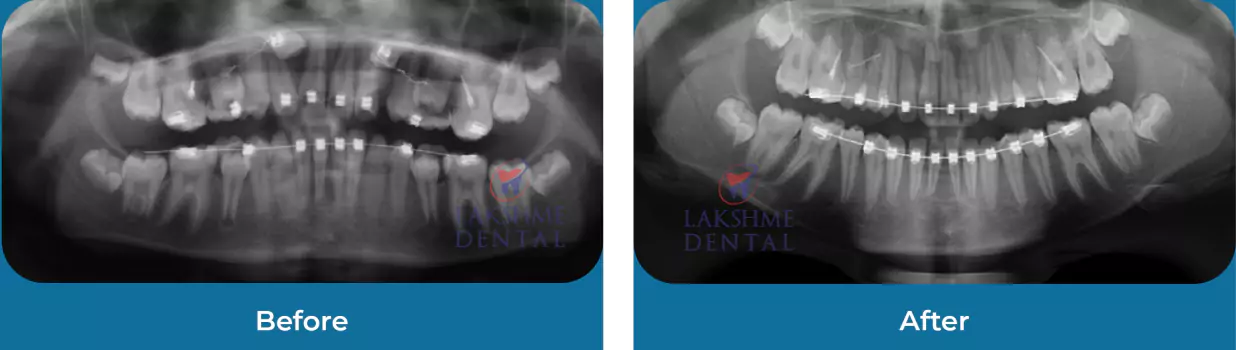

Surgical Orthodontics

Orthodontics

Full Mouth Rehabilitation